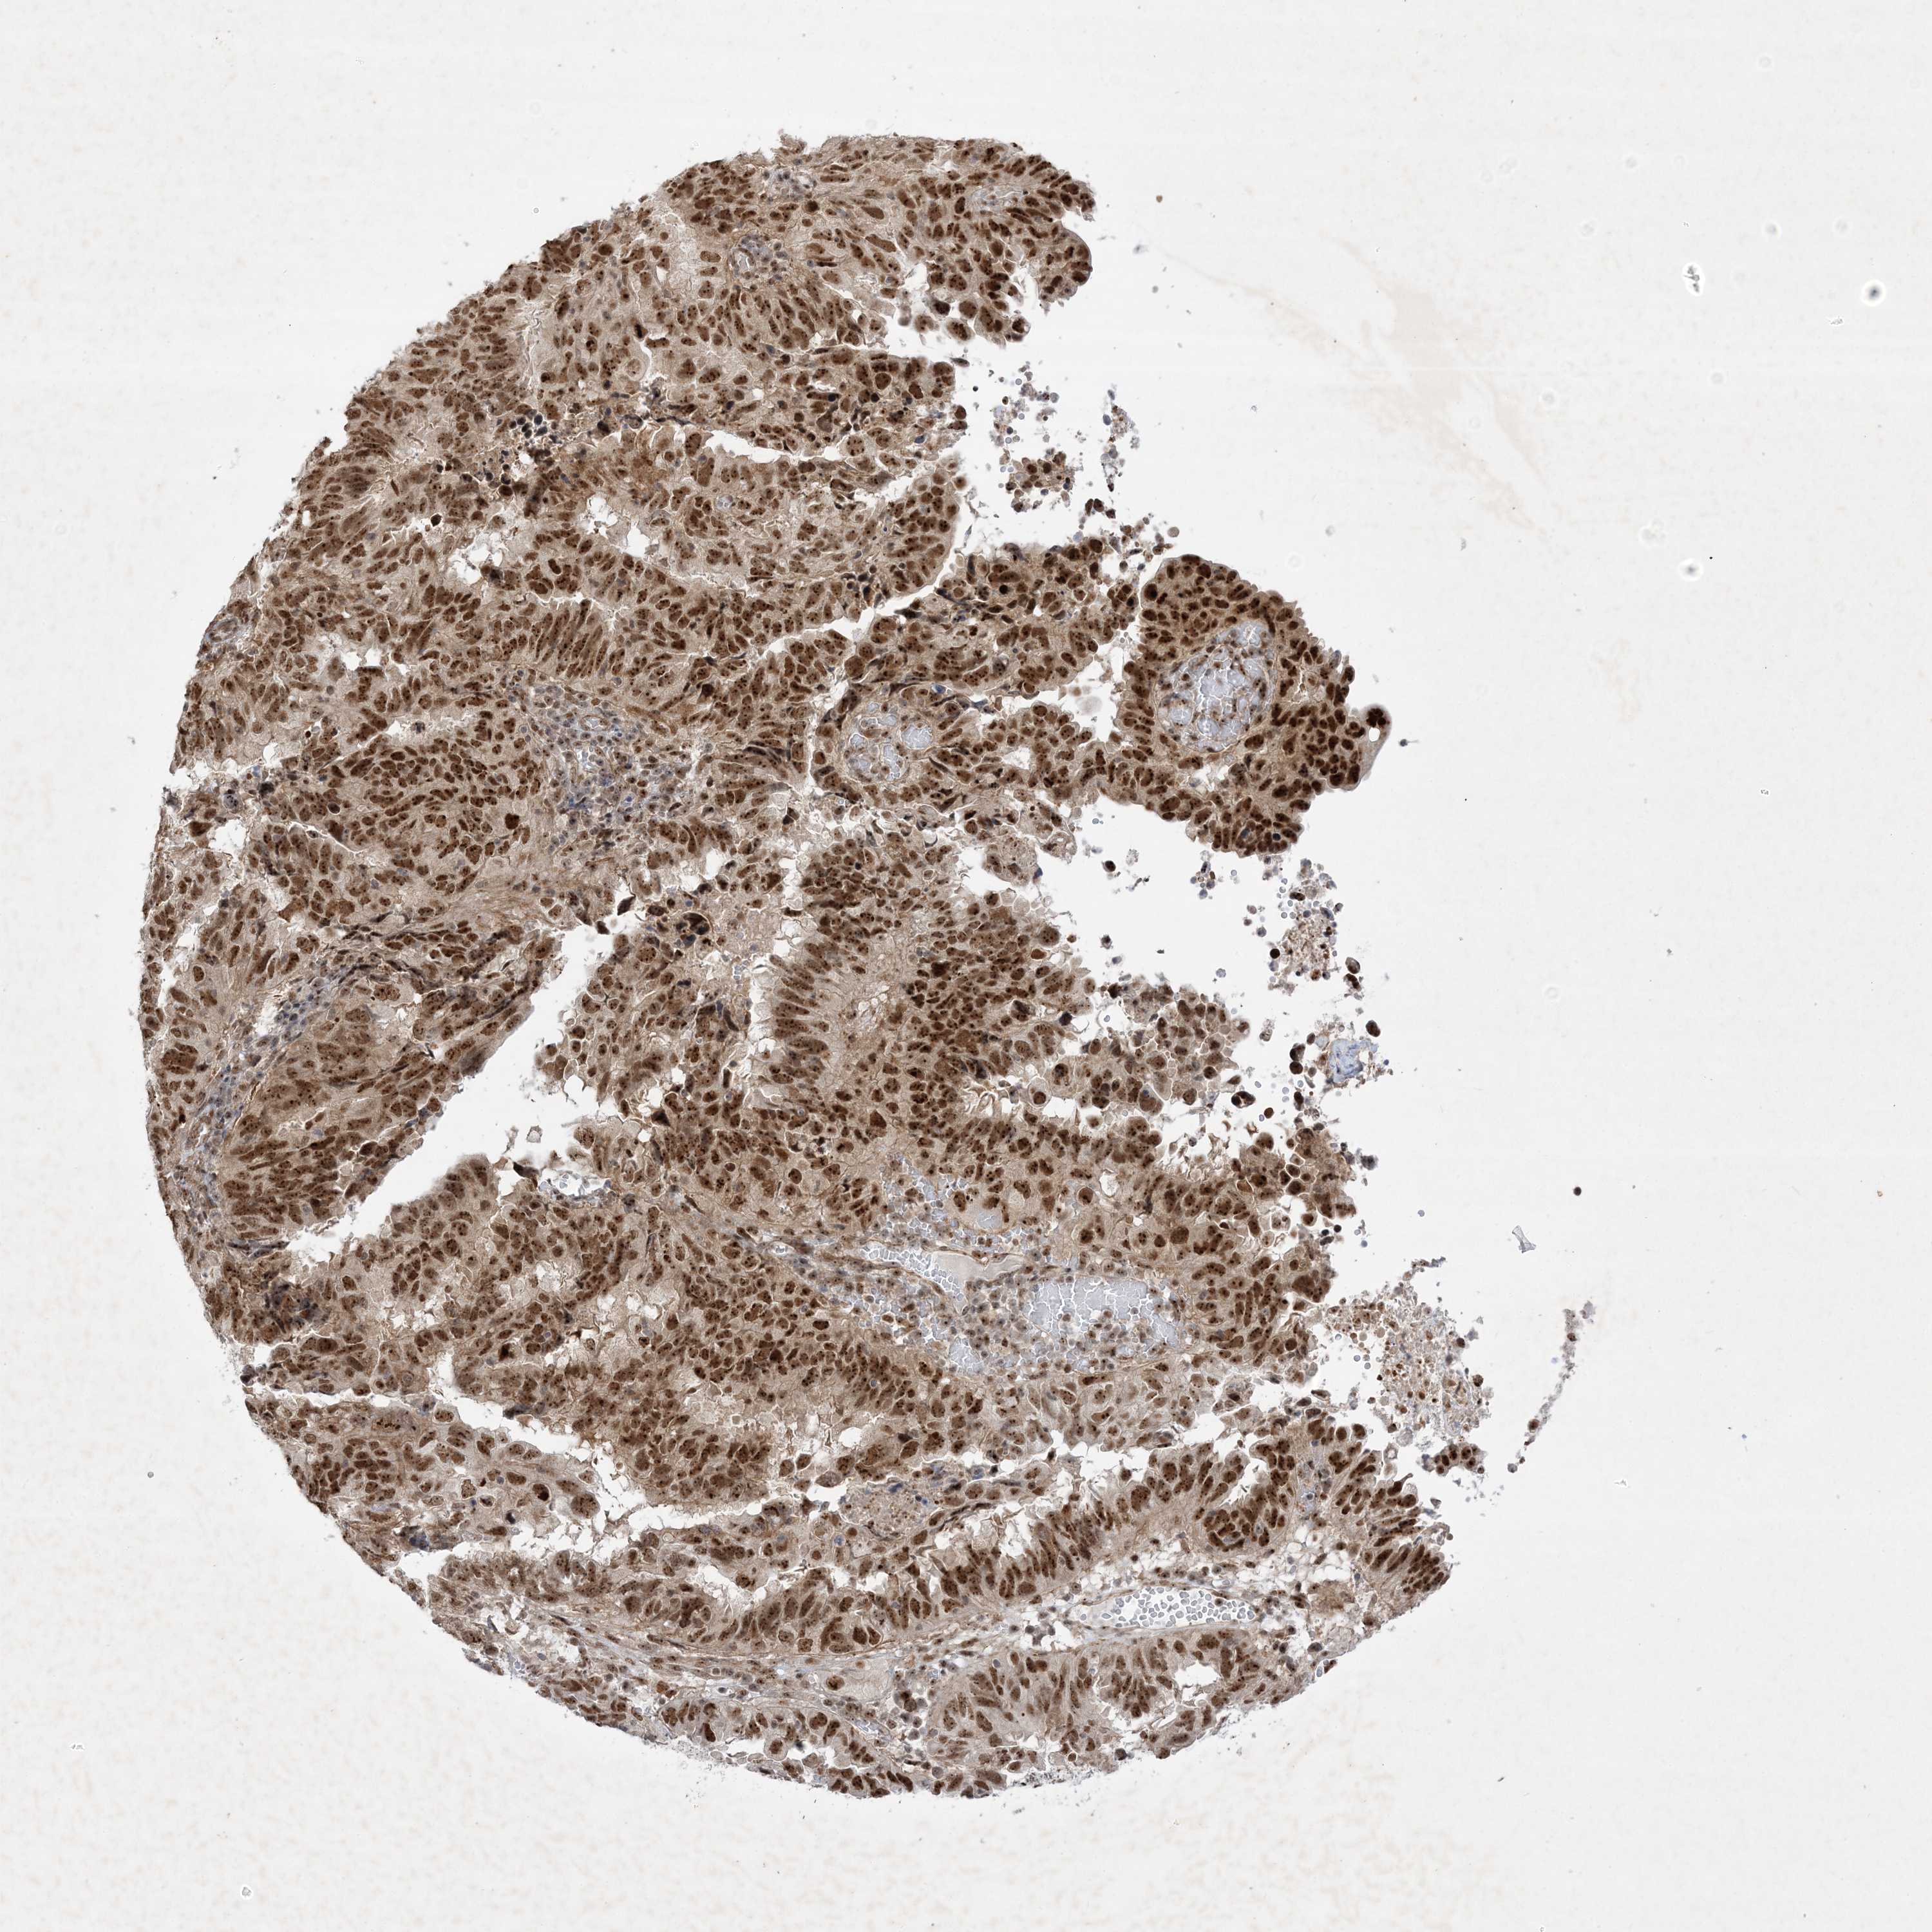

ENDOMETRIAL CANCER - Protein expressioni

A mouse-over function shows sample information and annotation data. Click on an image to view it in a full screen mode. Samples can be filtered based on level of antibody staining by selecting one or several of the following categories: high, medium, low and not detected. The assay and annotation is described here.

Note that samples used for immunohistochemistry by the Human Protein Atlas do not correspond to samples in the TCGA dataset.

Antibody stainingi

Antibody staining in the annotated cell types in the current human tissue is reported as not detected, low, medium, or high, based on conventional immunohistochemistry profiling in selected tissues. This score is based on the combination of the staining intensity and fraction of stained cells.

Each image is clickable and will lead to virtual microscopy that enables deeper exploration of all samples and also displays staining intensity scores, fraction scores and subcellular localization as well as patient and tissue information for each sample.

Antibody HPA036295

Antibody HPA036296

Staining

High

Medium

Low

Not detected

Intensity

Strong

Moderate

Weak

Negative

Quantity

>75%

75%-25%

<25%

None

Location

Nuclear

Cytoplasmic/membranous

Cytoplasmic/membranous,nuclear

Adenocarcinoma, NOS